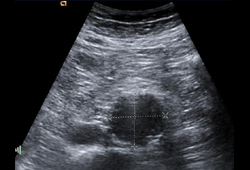

Abdominal aortic aneurysm

Ultrasound of a 3.8 cm x 4.2 cm AAA

University of Michigan, specifically the cases of Dr Upchurch reflecting the Departments of Vascular Surgery and Radiology